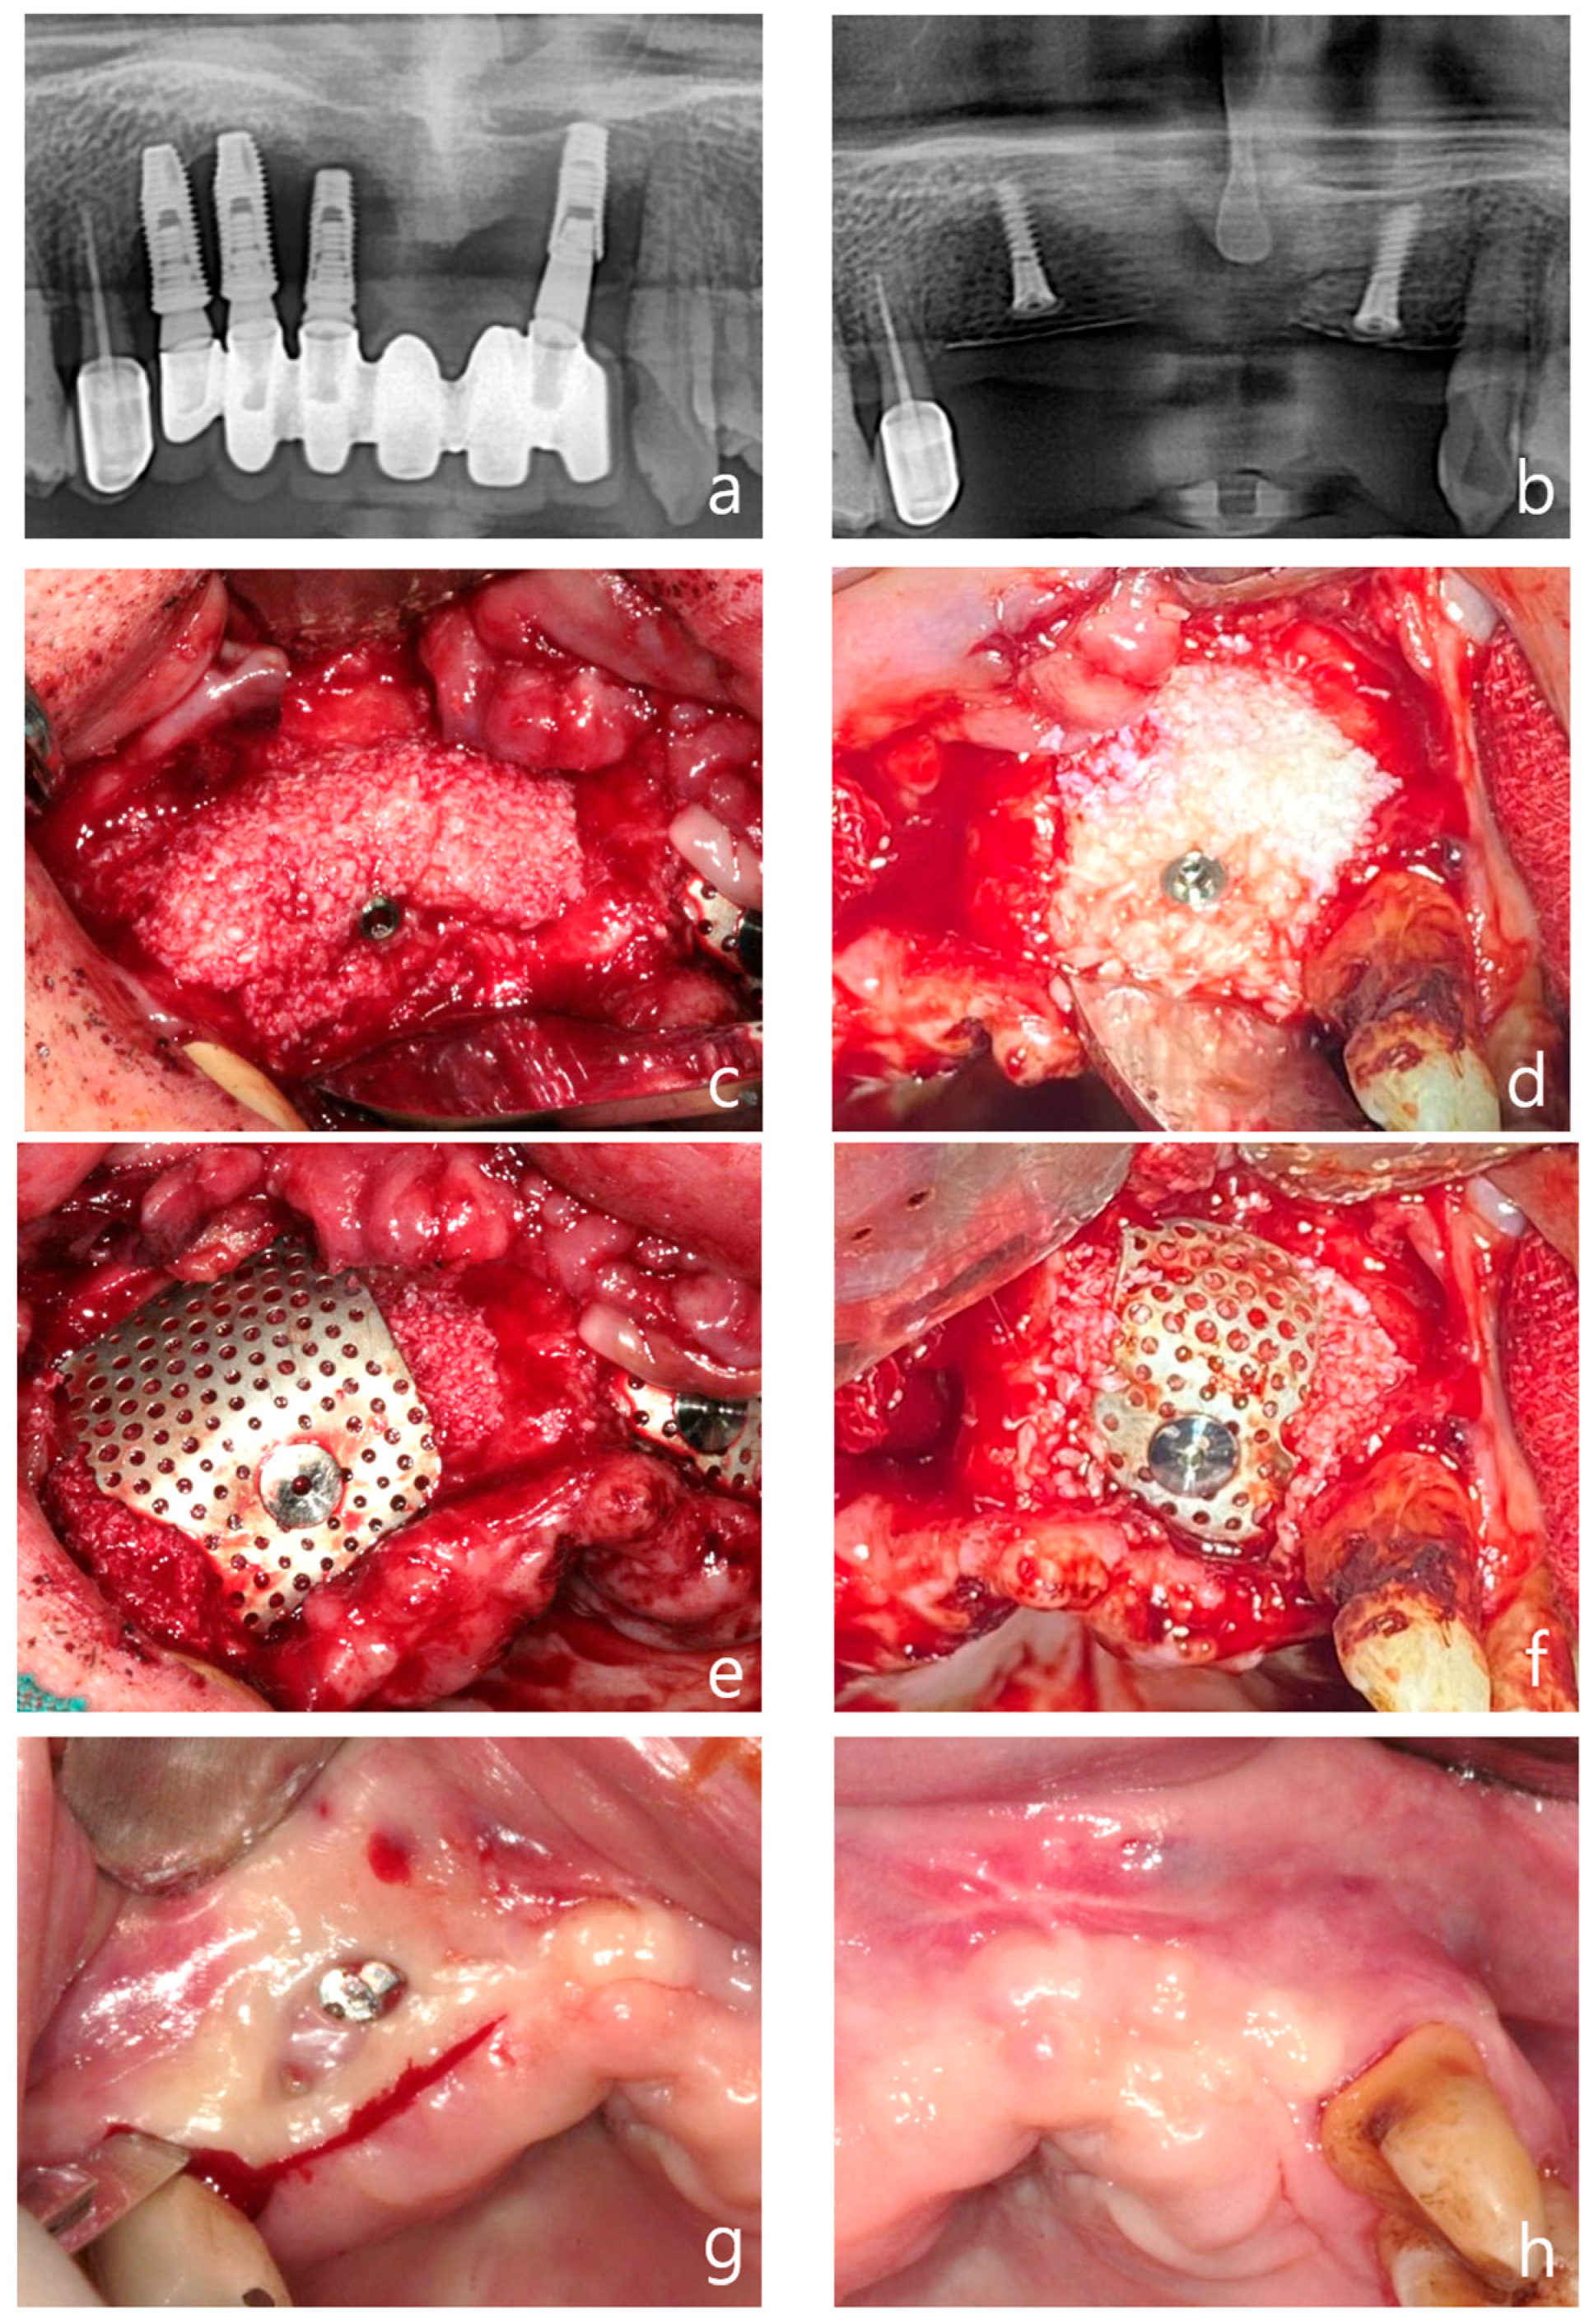

- Clinical efficacy: the combination of rhBMP-2 and a 3D-preformed titanium mesh (3D-PFTM) proved effective for reconstructing severely resorbed alveolar bone;

- Osteoinductive potential: rhBMP-2 demonstrated strong osteoinductive activity, even in patients with compromised bone regenerative capacity;

- Structural stability: the use of 3D-PFTM, particularly the OssBuilder system, provided reliable structural support for bone regeneration;

- Implant success: the combined approach resulted in stable bone regeneration and long-term implant success;

- Therapeutic value: the so called BOXAM (BMP-2, Oss-builder, xenograft, allograft, maintenance) technique appears to be a promising and reproducible strategy in dental and maxillofacial surgery.